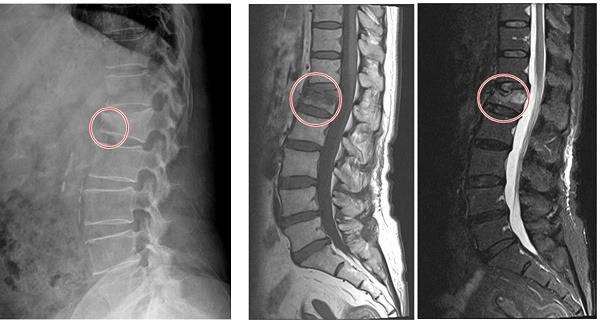

위산분비가 과도하게 억제되면 칼슘 흡수가 저하되고, 이는 직접적으로 뼈 건강에 악영향을 미친다. 특히 고용량으로 1년 이상 복용하는 경우 고관절, 손목, 척추 골절의 위험성이 급격히 높아진다는 연구 결과가 축적되고 있다.